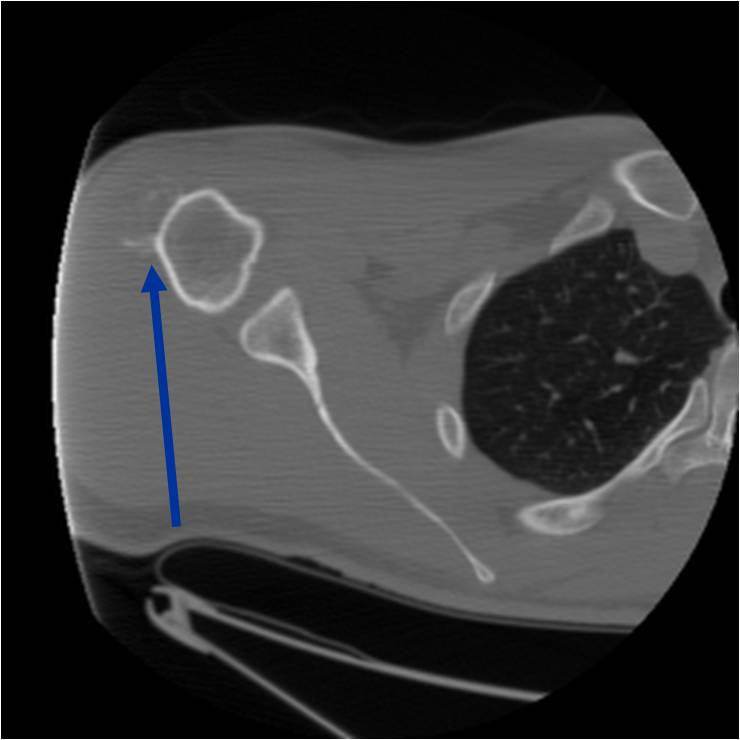

Radiographic Presentation

- Well circumscribed

- Appears to be embedded in underlying cortical bone

- Typically covered by a thin shell of reactive, often ossified periosteum

- Medullary cavity not grossly invaded